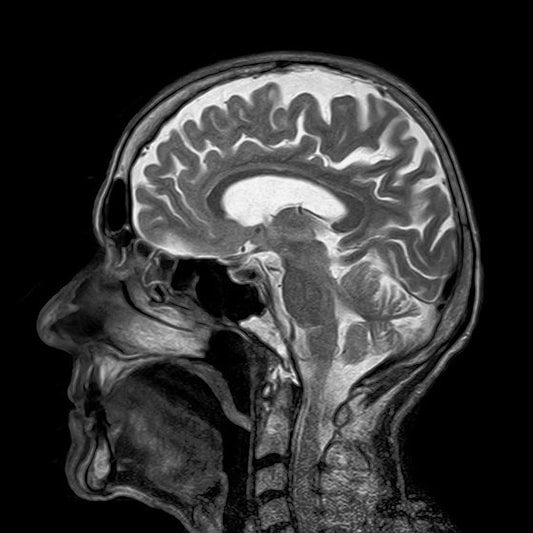

2. 영상 검사

파킨슨병 진단 시 가장 중요한 MRI 검사입니다.

MRI 검사를 통해 파킨슨병인지 아니면 뇌병변으로 인한 증상인지를 판별합니다.

그 외 영상검사로 파킨슨 PET입니다.

이 검사를 통해 파킨슨병의 주된 원인인 뇌의 도파민 소실의 정도를 확인합니다.